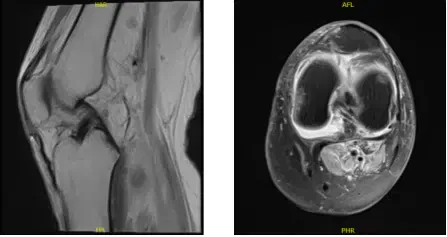

MRI-3T Rodilla Izquierda sin contraste

Desde entonces su dolor ha ido empeorando y no puede extender la rodilla. Ella usa un inmovilizador y muletas y niega fiebre o escalofríos. Hablamos sobre opciones de tratamiento como fisioterapia, resonancia magnética, inyección, cirugía y acordamos empezar con 3 Tesla MRI y fisioterapia como se había acordado.